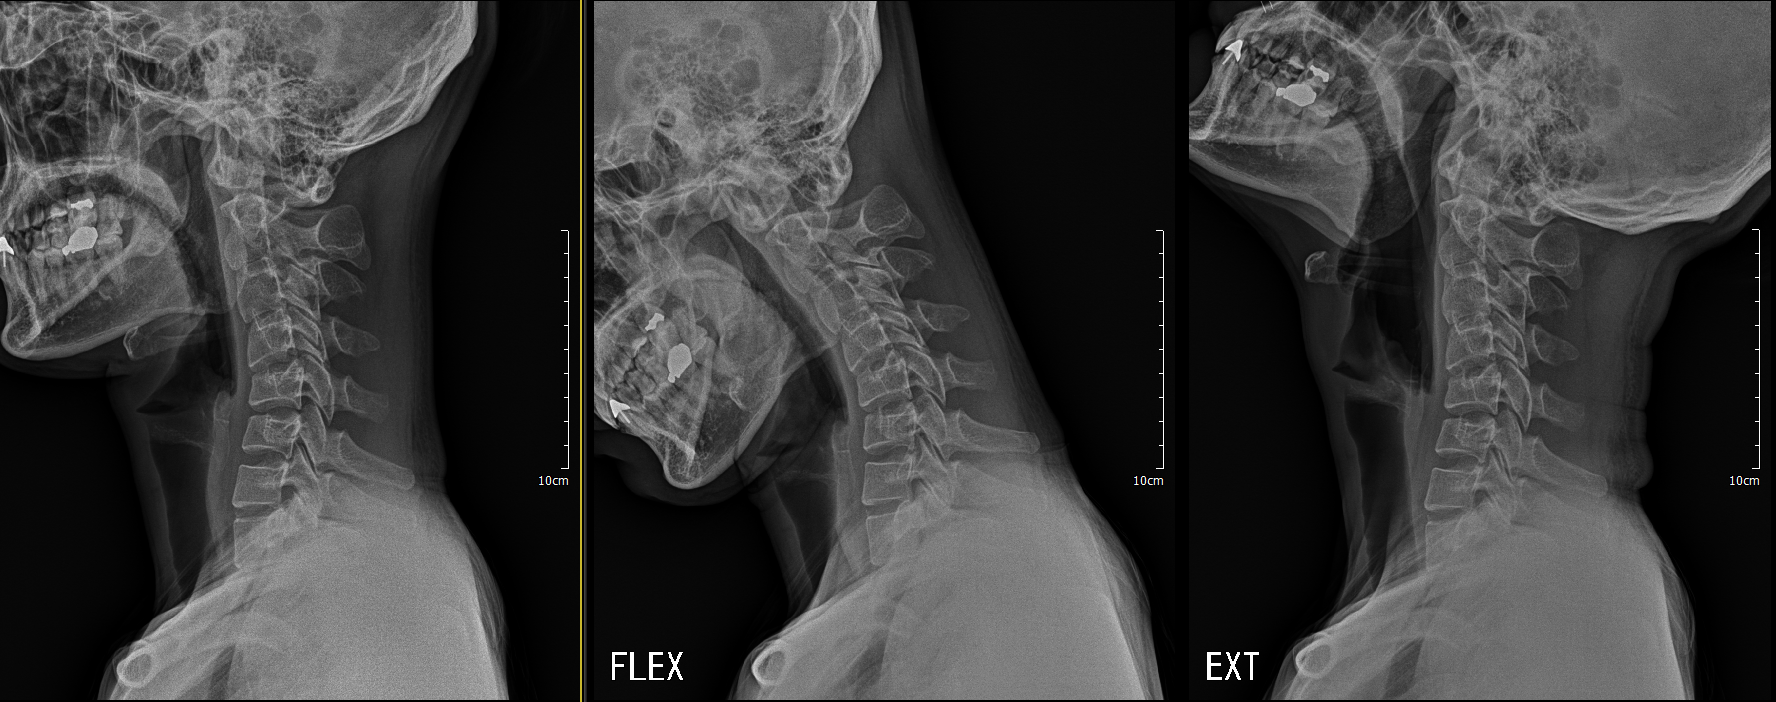

거북목 x ray 추가